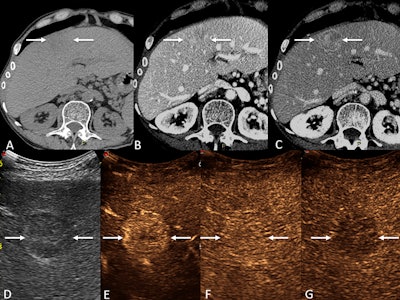

Images depict a 49-year-old female participant with cryptogenic cirrhosis who presented with a 3.2-cm liver lesion. This biopsy-confirmed hepatocellular carcinoma (HCC) with an initial categorization of Liver Imaging Reporting and Data System (LI-RADS) category LR-4 (probably HCC) at CT was upgraded to LR-5 (definitely HCC) at contrast-enhanced ultrasound (CEUS). (A) Precontrast CT images in the liver show vague hypoattenuation in the medial left hepatic lobe (arrows). (B) Arterial phase images demonstrate no definite arterial phase hyperenhancement (arrows). (C) Washout and an enhancing capsule (arrows) on a late-phase image resulted in an LR-4 categorization. (D) B-mode ultrasound shows a round hypoechoic nodule (arrows). (E) An early-phase CEUS image shows clear arterial-phase hyperenhancement (arrows); (F) No washout at one minute (arrows), and (G) late, mild washout at four minutes (arrows) resulted in a CEUS LR-5 categorization.RSNA